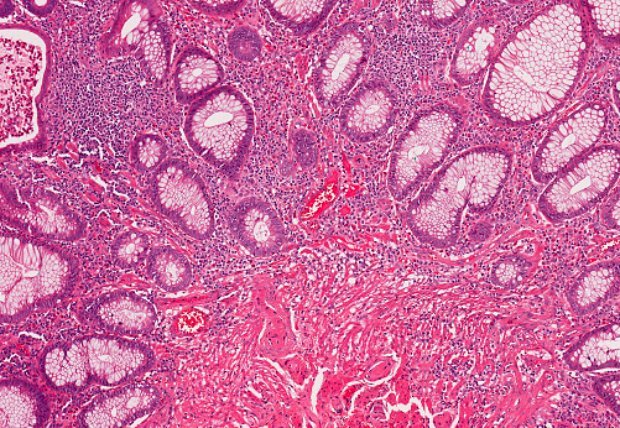

Diverticulitis is a condition that results from the inflammation of diverticula—pouch-like bulges that are found in the lower part of the large intestine. Diverticula in themselves are not harmful and are actually commonly found in adults over the age of 40, but when these pouches become infected, it can lead to the diagnosis of diverticulitis. ...click here to read more